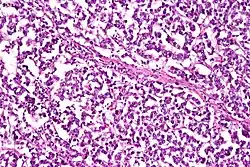

Dysgerminomas are comparable to testicular seminomas and account for approximately 32- 37% of all OGCTs.[1] They are particularly prominent in individuals with dysgenic gonads of 46, XY pure gonadal dysgenesis patients.[1] Based on gross examinations, dysgerminomas are characterized by having a ‘solid, lobulated, tan, flesh-like gross appearance with a smooth surface'.[1] Microscopically, the cellular structure is distinguished by a round-ovoid shape containing ample eosinophilic cytoplasm and an irregularly shaped nuclei.[1] The uniformly positioned cells are separated through the fibrous strands and lymphocytic infiltration is commonly observed.[4]